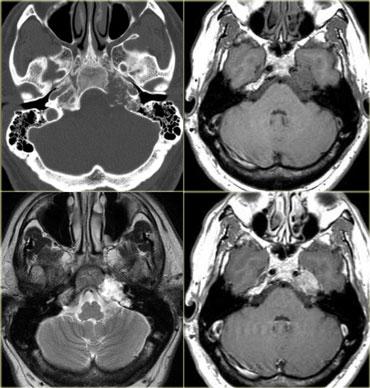

TRÁI: Di căn não. PHẢI: Nhiều u màng não và u thần kinh bao ở bệnh nhân U xơ thần kinh type II (Neurofibromatosis II)

Bệnh đa ổ

Nhiều khối u trong não thường gợi ý bệnh di căn (hình minh họa).

Các u não nguyên phát thường gặp ở một vùng duy nhất, nhưng một số u não như u lympho, u nguyên bào đa hình đa trung tâm (multicentric GBM) và u thần kinh đệm lan tỏa não (gliomatosis cerebri) có thể đa ổ.

Một số khối u có thể đa ổ do di căn gieo rắc: điều này có thể xảy ra trong u nguyên tủy bào (PNET-MB), u màng nội tủy (ependymoma), u nguyên bào đa hình (GBM) và u tế bào ít nhánh (oligodendroglioma).

U màng não và u thần kinh bao có thể xuất hiện nhiều ổ, đặc biệt trong bệnh u xơ thần kinh type II.